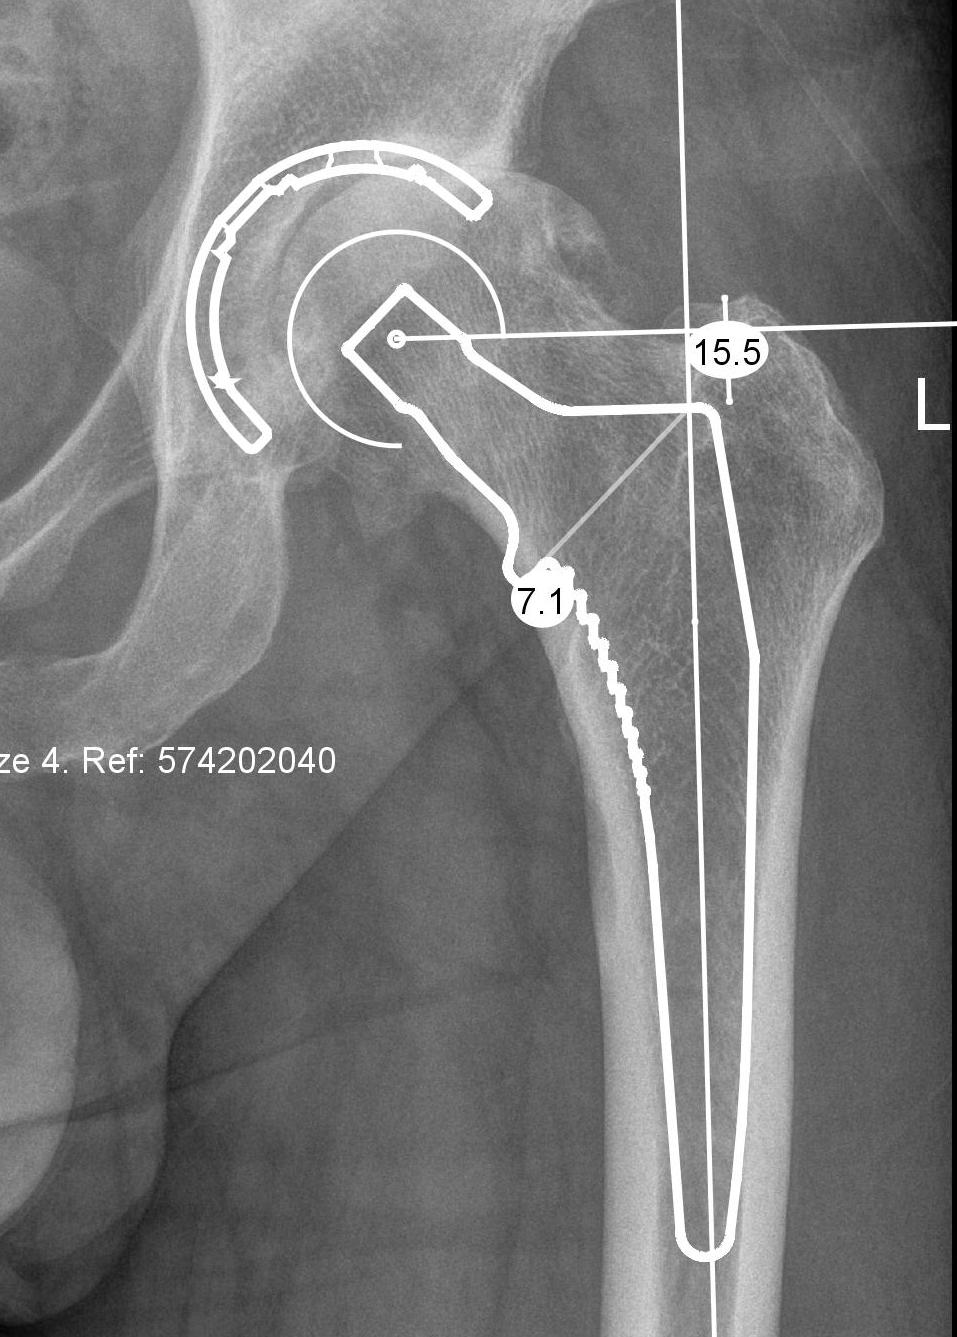

1.  Radiographic 2D preoperative templating

TemplateTemplate